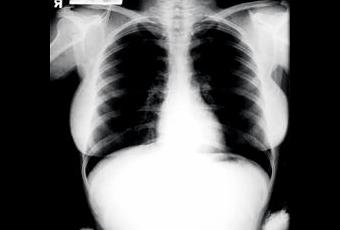

Ce week-end se tenait l'annuelle Julien's Auction, autrement dit, la vente aux enchères au Planet Hollywood Resort et Casino de Las Vegas. Et parmi les nombreuses pièces proposées, il y en avait un "nu" de Marylin Monroe qui a trouvé preneur pour une coquette somme d'argent. On cite 45.00 $. Pour rappel, l'année dernière, la même vente avait récolté 5.000$ pièce, pour quelques X-Ray du KIng Elvis. Mais attention, ne croyez pas qu'un nu intégral de Monroe se soit trouvé ainsi jeté en pâture. Il s'agit égalemnt d'un X-Ray des poumons de la Diva, pris en 1954 au Cedar's Lebanon Hospital devenu entretemps Le Cedar-Sinaï Medical ,alors que la rumeur de l'époque faisait état d'une éventuelle grossesse, suivie d'une fausse-couche de MM. En tout il y a quatre clichés dont un de son abdomen. Question. Comment ces clichés ont-ils filtré extra-muros du centre hospitalier où ils ont été stockés? Mystère! Comme la mort de l'icône. Marylin, et cela ne surprend plus personne, a toujours été entourée d'un épais mystère..même 48 ans après son décès!

utres objets ont fait l'objet de cette vente exceptionnelle, à savoir le divan sur lequel M.M. s'tendait alors qu'elle consultait chez le Dr Greeson, ainsi qu'une carte postale et le script de son dernier film "Someting's Got to Give" inachevé, comme chacun sait.